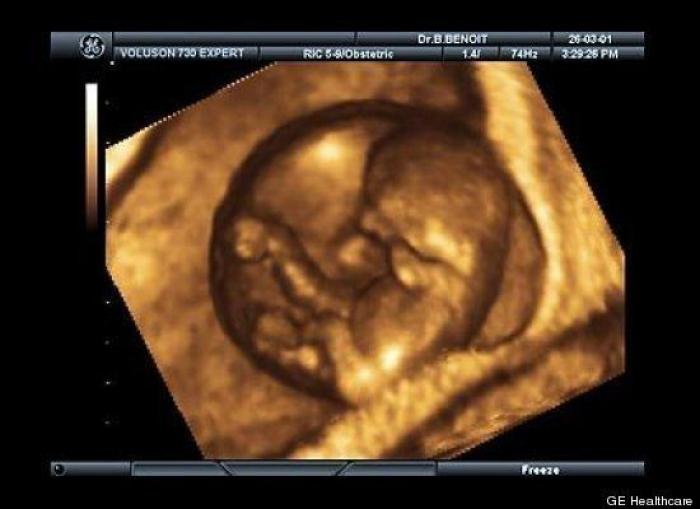

En esta galería puedes ver en fotos como es el desarrollo de un feto de semana en semana:

Desarrollo del feto, en fotos